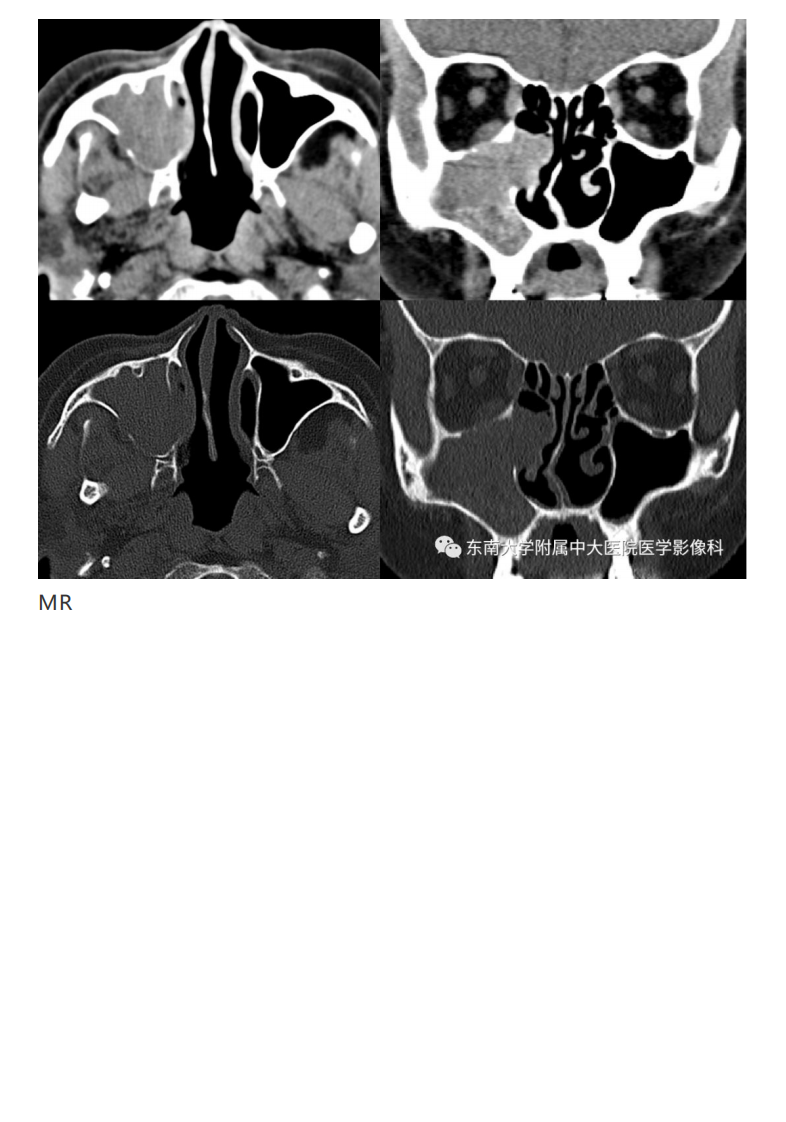

20190325_2【晨读结果公布】2019.03.25头颈部系统疾病.pdf